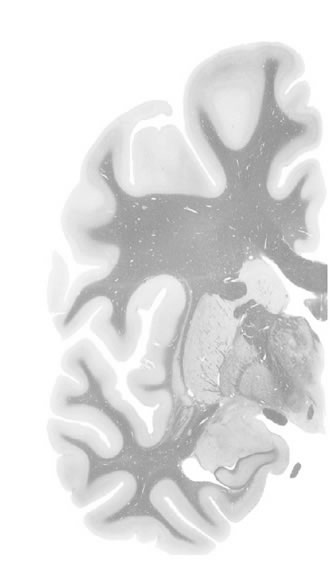

Hi-Resolution Sections · Cells (Nissl Staining) · Virtual Microscopy

Frontal sections (Nissl) from the Atlas Brain:

Slice ID:

r3-1082

Plate NR:

ca 28-29

Position:

8,5 mm